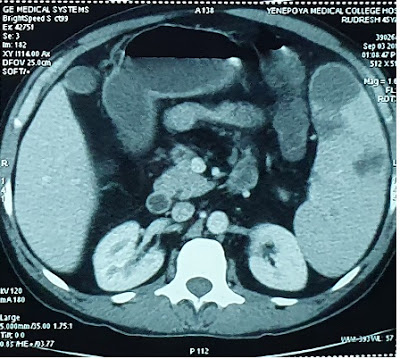

Later CECT was done which showed – hepatosplenomegaly with hypoechoic lesions in spleen s/o infarct as shown in Fig1 and Fig 2